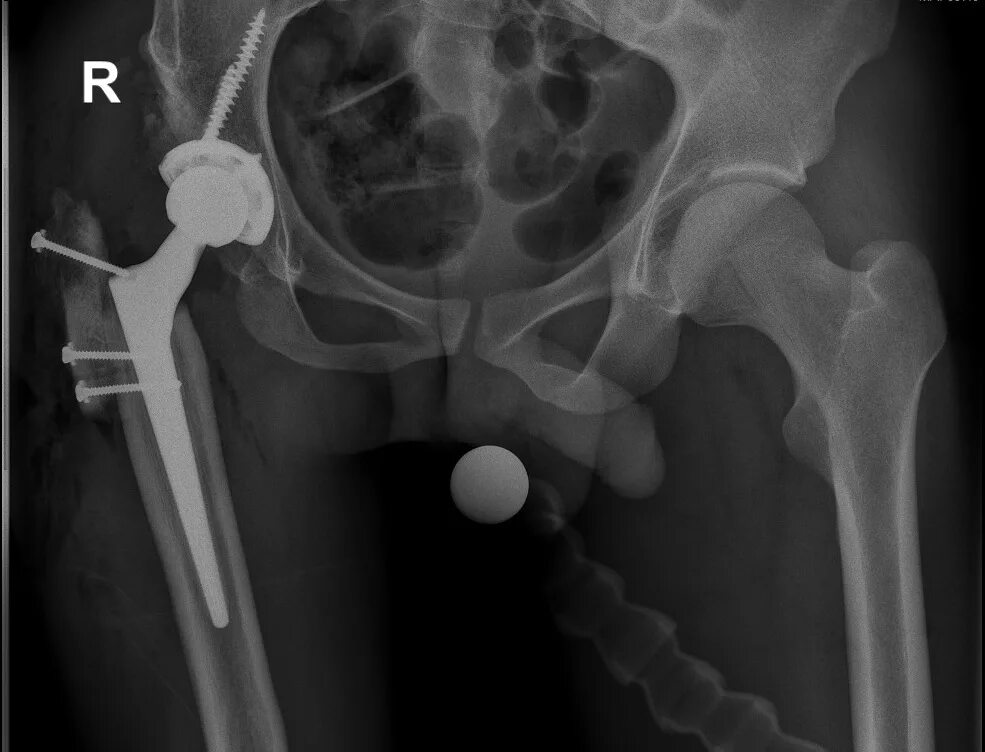

Анкилоз тазобедренного сустава